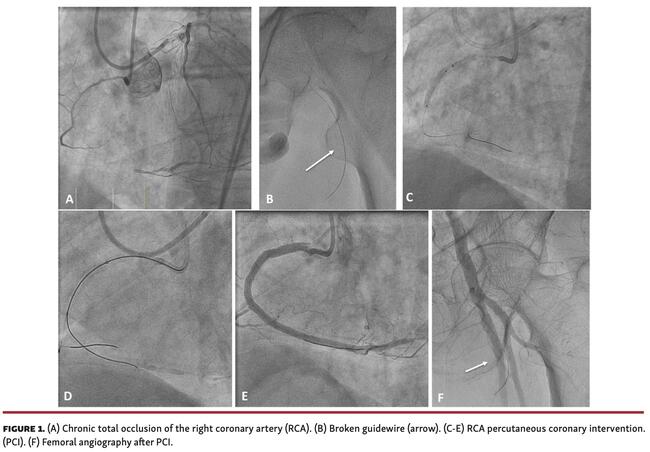

A 72-year-old patient underwent percutaneous coronary intervention (PCI) of a right coronary artery (RCA) chronic total occlusion (CTO) (Figure 1A). During the femoral puncture, a plastic guidewire could not advance, so it was removed. A second fluoroscopy-guided puncture was performed, visualizing a broken piece of the wire apparently at the femoral artery (Figure 1B). PCI was continued because a subintimal position was suspected. After intravascular lithotripsy and stenting of the proximal right coronary artery (RCA) (Figure 1C) using a dual-lumen microcatheter (Figure 1D), PCI was successfully completed (Figure 1E; Video 1). A final angiography of the femoral artery confirmed that it remained in the same position, so it was left there (Figure 1F; Video 2).